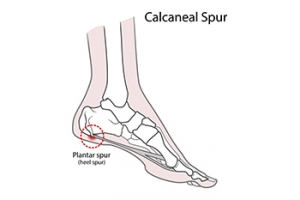

How Are Heel Spurs Treated?

A heel spur is also known as a calcaneal spur and is a bony growth formed by calcium deposits on the underside of the foot. They can have a pointy, hooked, or shelf-like shape. Heel spurs are the body’s way of trying to protect the foot from another foot condition, such as plantar fasciitis. Heel spurs can also arise from arthritis, overuse, obesity, and improper footwear. These growths do not always cause pain but when they do, the heel can be tender, with dull or sharp pain when standing. Usually, it is the underlying condition that causes the pain. Women are more likely to get heel spurs than men. A diagnosis will consist of a visual examination of the foot and understanding where the pain arises with movement, as well as an X-ray, which will highlight the bony growth. If you have a heel spur that is causing you discomfort, it is suggested that you make an appointment with a podiatrist to discuss treatment options of the spur itself or the underlying condition which may be causing it.

Heels Spurs

Heel spurs are formed by calcium deposits on the back of the foot where the heel is. This can also be caused by small fragments of bone breaking off one section of the foot, attaching onto the back of the foot. Heel spurs can also be bone growth on the back of the foot and may grow in the direction of the arch of the foot.

Older individuals usually suffer from heel spurs and pain sometimes intensifies with age. One of the main condition's spurs are related to is plantar fasciitis.

Pain

The pain associated with spurs is often because of weight placed on the feet. When someone is walking, their entire weight is concentrated on the feet. Bone spurs then have the tendency to affect other bones and tissues around the foot. As the pain continues, the feet will become tender and sensitive over time.

Treatments

There are many ways to treat heel spurs. If one is suffering from heel spurs in conjunction with pain, there are several methods for healing. Medication, surgery, and herbal care are some options.

How to Treat Heel Spurs

Heel spurs are calcium deposits that cause bone protrusions on the heel bone. Heel spurs are usually associated with plantar fasciitis, which occurs when the plantar fasciitis in the foot becomes inflamed. Typically, heel spurs don’t cause any symptoms. However, they can produce chronic or intermittent heel pain. Those who have had the condition often describe the irritation as a stabbing pain.

There are risk factors that may make you more likely to develop heel spurs. People who have abnormal walking gaits, run and jog on hard surfaces, are obese, or wear poorly fitting shoes are more likely to develop heel spurs.

Fortunately, there are precautions you can take to avoid developing heel spurs. One of the best ways to do this is by wearing well-fitting shoes with shock-absorbent soles. Another preventative technique is to choose running shoes if you plan on running, and walking shoes if you plan on walking. Shoes are made for different activities and it is important to research a shoe before you purchase a pair.

The pain associated with heel spurs often decreases the more you walk. However, a recurrence of pain after an extended period of rest or walking is likely to occur with this condition. Those with severe heel spur pain may opt to go the surgical route for treatment. However, more than 90% of those with the condition get better without surgical treatment. If you have a heel spur and want to know if surgery is right for you, you should go to your podiatrist and he or she will be able to conduct a pre-surgical test or exam to determine if you are an optimal candidate for surgery.